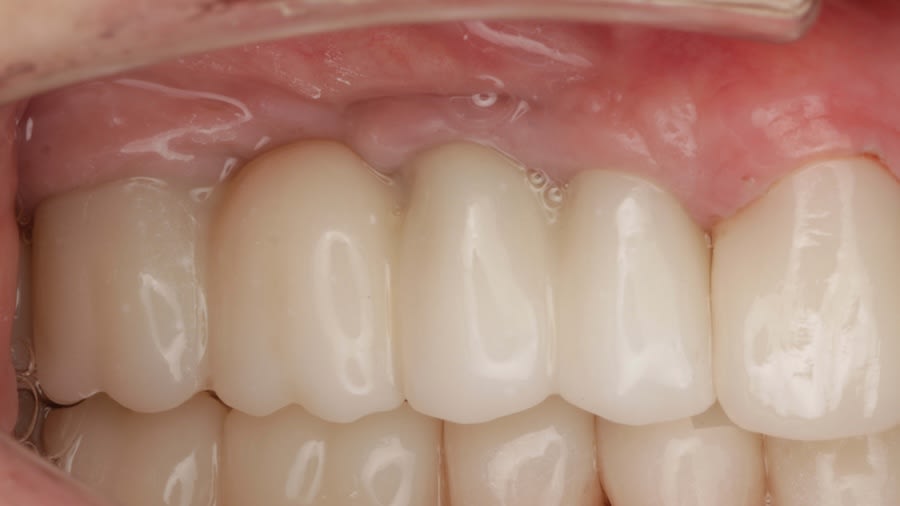

Case 1 (Figure 3 through Figure 24) depicts a 3-year follow-up of combined osseodensification sinus protocol IV in a severely resorbed maxillary ridge with ≤0.5 mm bone height in molar sites and horizontal deficiency at the first premolar site, using a two-stage approach for implant placement.

The presented protocol describes a crestal sinus elevation procedure using osseodensification burswith vertical stops (Versah) in severe cases with <2 mm of residual bone as a predictable technique, with successful bone regeneration for second-stage implant placement with subsequent stable peri-implant bone level at 3-year follow-up. This technique, thus, offers a simplified, minimally invasive, and less traumatic method for sinus floor elevation in cases with severe residual bone height loss.